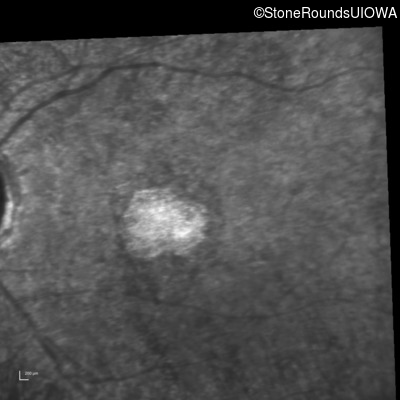

Infrared Fundus Photograph - Left - 20/500 sc

Exemplar